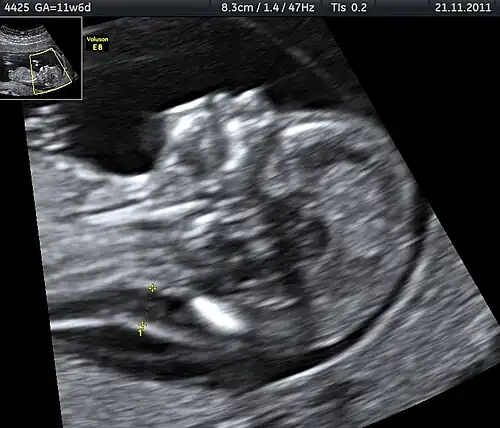

A nuchal scan or nuchal translucency (NT) scan/procedure is a sonographic prenatal screening scan (ultrasound) to detect chromosomal abnormalities in a fetus, though altered extracellular matrix composition and limited lymphatic drainage can also be detected.[1]

There are two distinct measurements: the size of the nuchal translucency and the thickness of the nuchal fold. Nuchal translucency size is typically assessed at the end of the first trimester, between 11 weeks 3 days and 13 weeks 6 days of pregnancy.[3] Nuchal fold thickness is measured towards the end of the second trimester. As nuchal translucency size increases, the chances of a chromosomal abnormality and mortality increase; 65% of the largest translucencies (>6.5mm) are due to chromosomal abnormality, while fatality is 19% at this size.[2] A nuchal scan may also help confirm both the accuracy of the pregnancy dates and the fetal viability.

Procedure

Nuchal scan (NT procedure) is performed between 11 and 14 weeks of gestation, because the accuracy is best in this period. The scan is obtained with the fetus in sagittal section and a neutral position of the fetal head (neither hyperflexed nor extended, either of which can influence the nuchal translucency thickness). The fetal image is enlarged to fill 75% of the screen, and the maximum thickness is measured, from leading edge to leading edge. It is important to distinguish the nuchal lucency from the underlying amniotic membrane.[9]

Normal thickness depends on the crown-rump length (CRL) of the fetus. Among those fetuses whose nuchal translucency exceeds the normal values, there is a relatively high risk of significant abnormality.